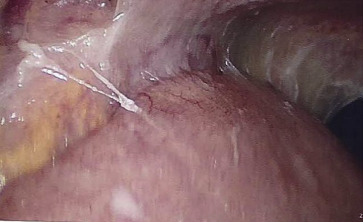

Esophagogastroduodenoscopy to exclude malignancy revealed a shallow ulcer at the antrum, and colonoscopy revealed a serrated adenoma in the transverse colon. Diagnostic laparoscopy revealed that the omentum was adherent to the abdominal wall (Fig. 3 ) and the presence of diffuse white nodules in the peritoneum (Fig. 4 ). A peritoneal biopsy showed chronic granulomatous inflammation. The polymerase chain reaction for tuberculosis was positive. The diagnosis of tuberculous peritonitis was reached, and antituberculosis treatment was started. The ascitic fluid culture yielded the same result 2 months later.

Laparoscopy. The omentum is adherent to the abdominal wall.